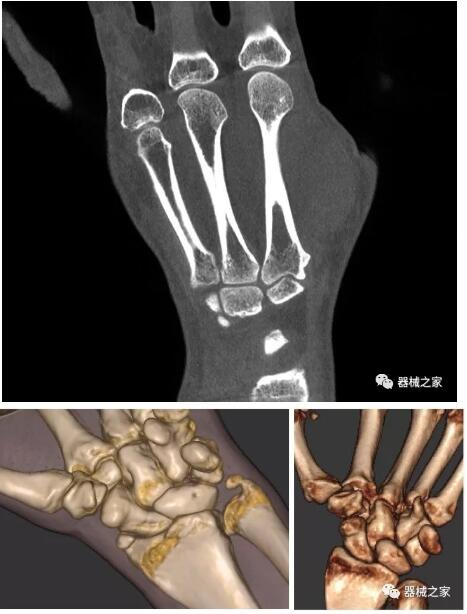

以下是這些“特立獨行”的CT所拍出來(lái)的圖像: